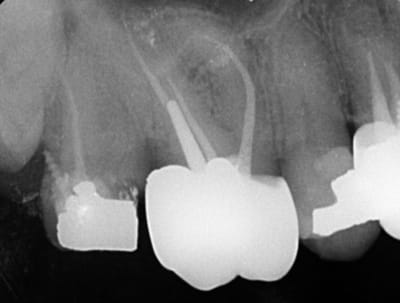

Moi j'ai fait ça la semaine dernière (et je ne suis vraiment pas fier).

Pas de douleurs pas de saignement au forage. La patiente me dit: ah, j'ai un peu mal quand j'appuis dessus...

Que feriez vous?

Finalement, séance suivante: mise en évidence d'un saignement dans le logement du tenon.

Obturation à la biodentine que j'ai fait "descendre dans le logement du tenon " avec un insert fin sans eau.

Disparition des symptômes la semaine suivante.

Contrôle à 6 mois, dent asymptomatique, radio encourageante.